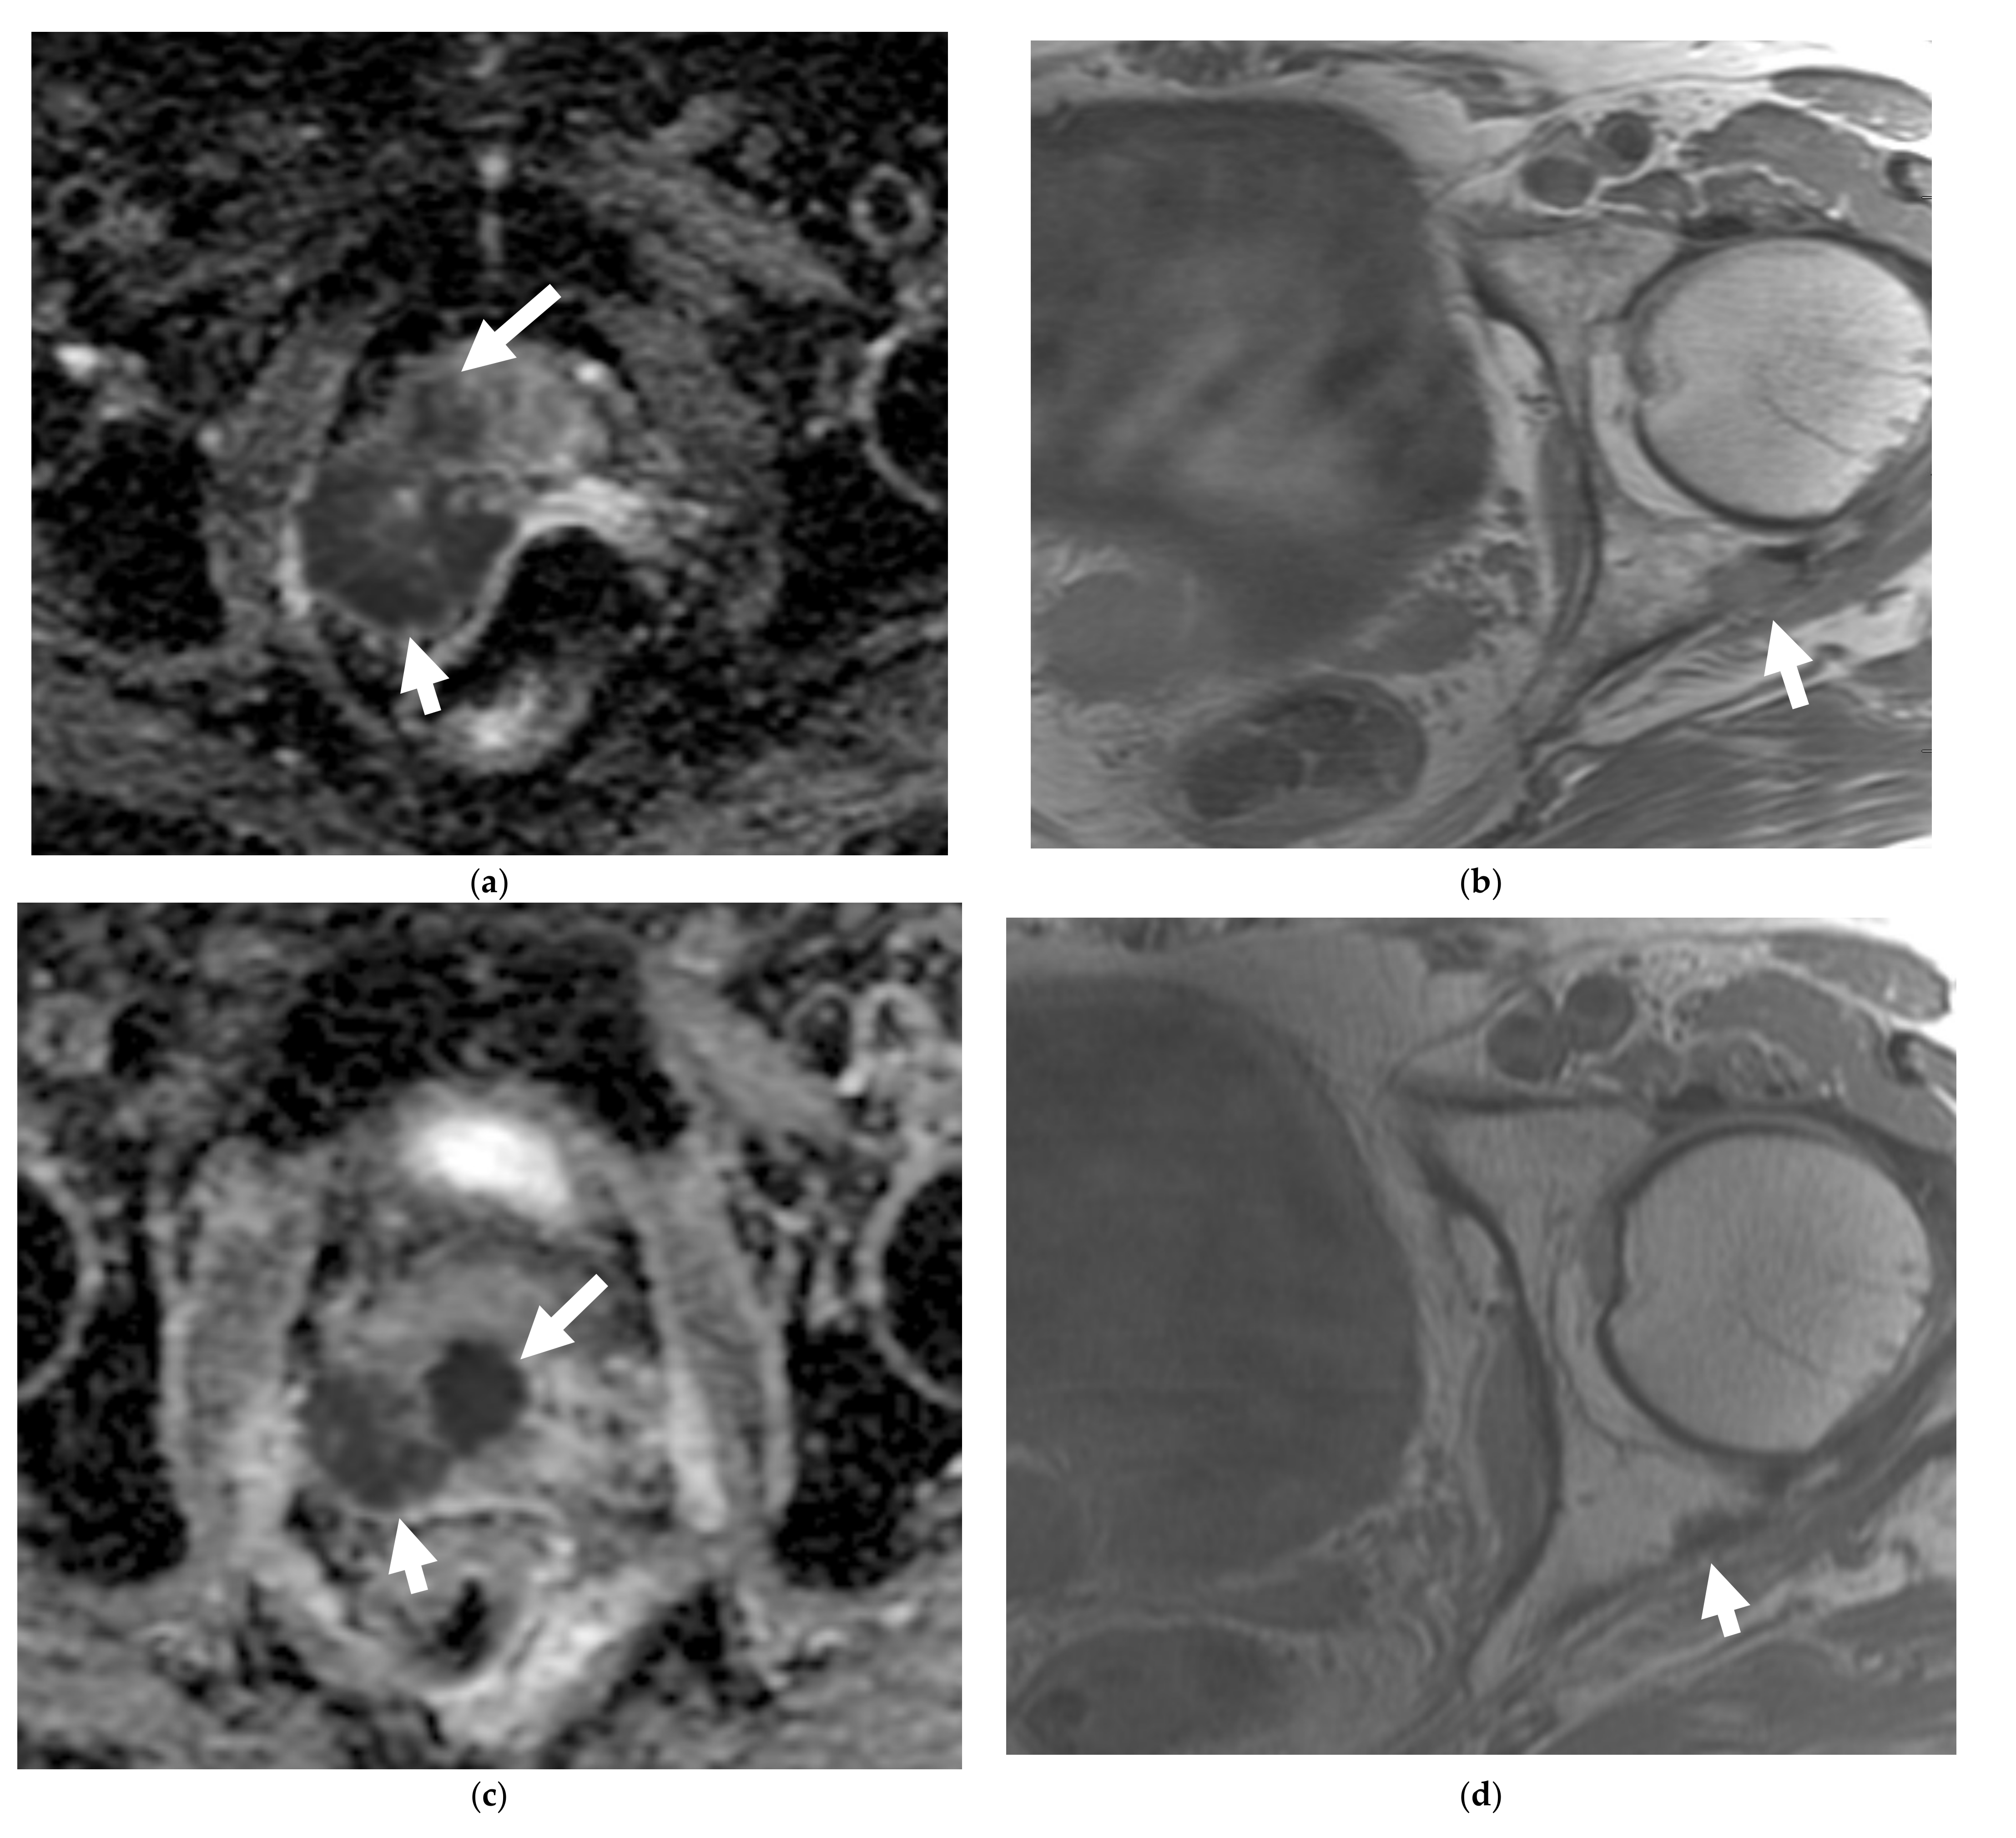

A 56-year-old male with prior hormonal therapy for 2 years and external beam radiation therapy for the biopsy-proven diagnosis of prostatic adenocarcinoma in 2008. Follow-up MRI pelvis performed for recurrent elevated serum PSA 6 years after shows a left posterolateral peripheral zone prostatic nodule with restricted diffusion on ADC map (a) and avid early enhancement on the dynamic postcontrast T1W images (b), suspicious for recurrent prostatic neoplasm (arrow). This was biopsy proven to be prostatic adenocarcinoma. Further follow-up MRIs after 12 years showed rapidly enlarging left prostatic neoplasm (long arrow) with regional left internal iliac lymphadenopathy (short arrow) on ADC image (c) along with metastatic left common iliac and retroperitoneal lymphadenopathy. This was biopsy proven to be metastatic prostatic neuroendocrine carcinoma. Prostatic mass showed heterogeneous hypermetabolism on the axial color fused image of the Ga-68 DOTATATE PET-CT (d). The nodal metastases (arrow) were without suspicious hypermetabolism due to poorly differentiated neuroendocrine neoplasm/carcinoma component.

Multiparametric MRI (mpMRI) is now considered to be the standard imaging evaluation of choice when suspecting prostate cancer. Members of PI-RADS (version 2.1) steering committee recommend using 3T MRI scanners over 1.5T machines for prostatic evaluation, as it increases the signal-to-noise ratio (SNR), leading to an increase in both temporal and spatial resolution. If only 1.5T scanners are available or in the case of inherently low SNR sequences, such as DWI, they recommend the use of endorectal coil (ERC) which has the ability to increase SNR at any magnetic field strength [32]. Most tumors appear isointense to normal prostate tissue on T1-weighted sequences which serve as a baseline for the contrast-enhanced MRI, delineate the prostate outline, and can also demonstrate post-biopsy hemorrhage and periprostatic fat invasion. T2-weighted (T2W) sequences are used to evaluate prostatic zonal anatomy, primarily evaluate the transitional zone or central gland tumors, asses for seminal vesicle or nodal involvement, and detect extra-prostatic extension (EPE). Peripheral zone cancers usually demonstrate ill-defined T2 hypointense focal lesions with restricted diffusion and are primarily evaluated on ADC/DWI images (Figure 1). Transitional zone tumors appear hypointense with spiculated, ill-defined margins and smudgy appearance on T2W images. These lesions may also invade the urethral sphincter and anterior fibromuscular stroma [33,34]. While mpMRI is now considered the technique of choice for initial and local (T) tumor staging, PET/CT and PET/MRI have shown a great value in distant extraprostatic (N and M) staging (Figure 2), restaging after biomedical relapse, and response assessment after androgen deprivation therapy (ADR) [35,36,37,38]. The sensitivity, specificity, positive predictive value, and negative predictive value of multiparametric MRI for detection of EPE (Figure 3), were 48.7%, 73.9%, 35.9%, and 82.8%, respectively [39,40].

There is no core difference in staging between prostatic adenocarcinoma and NEPCs. The TNM staging system, developed by the American Joint Committee on Cancer (AJCC), is the most commonly used staging method to assess the tumor status (T), lymph nodes (N), and metastasis (M) [70]. Unlike prostatic adenocarcinoma, clinical tumor stage 1 is uncommonly seen in cases with NEPC and they usually present with higher stages, with more visceral and nodal metastases with predominantly lytic bone lesions. Hence, NEPC is clinically suspected when a prostate cancer is seen with absent or a low/moderate rise in PSA, presents at advanced stage, or has a predominance of visceral and/or bone metastatic disease (Figure 2). In addition, NEPC is also suspected when the prostate cancer becomes unresponsive to ADT with rapid disease worsening (Figure 3 and Figure 4) [68,69]. Paraneoplastic syndrome is also a potential distinguishing feature for NEPCs, especially SCNC, with Cushing’s syndrome being the most common manifestation [71,72]. Currently, the reference standard for the diagnosis of NEPCs is pathologic examination showing the above microscopic features, plus the presence of neuroendocrine IHC markers, e.g., NSE, SYN, and CgA [16,73].